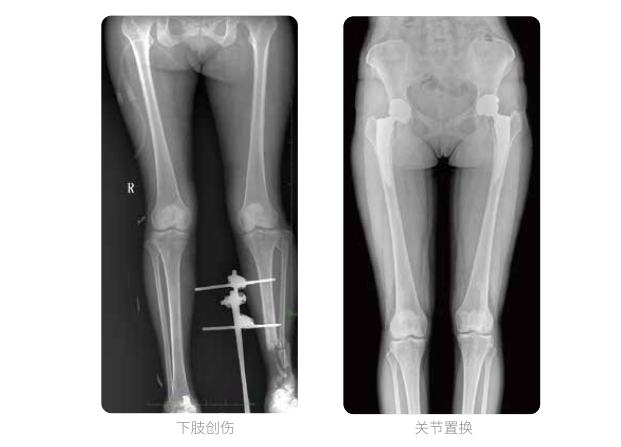

近年來,脊柱及下肢畸形的患者較多,多發于青少年的脊柱側彎畸形,骨性關節炎、風濕性關節炎以及雙下肢畸形如膝關節內外翻、X型O型腿等也是骨科常見病。并且發病率呈現逐年升高的趨勢,常常累及下肢髖、膝、踝3個負重關節,影響患者生活,甚至喪失工作能力。

在脊柱及下肢畸形的臨床治療過程中,一般需要進行矯正手術治療,在對其進行手術前后,均需要拍攝X光片以便分析病情、明確診斷和觀察治療效果。常規DR拍攝面積有限,最大規格僅有43cm,但成人男性全脊柱長度平均為70-75cm,女性為66-70cm,而雙下肢更長。普愛醫療PLX8600動態DR的43cm*86cm超大有效視野,可一次性拍攝全脊柱、雙下肢的影像視野。

普愛醫療動態數字化X線攝影(動態DR)擁有43cm*86cm超大有效視野,使全脊柱及雙下肢能夠得到完整清晰的成像,為臨床在脊柱側彎畸形和下肢骨關節病變診斷、治療方案制定及治療后復查提供精準的測量。

雙下肢臨床影像

普愛醫療動態數字化X線攝影(動態DR)可以整體顯示雙髖至雙踝關節,直觀的展示因關節軟骨磨損和軟組織不平衡所造成的畸形及力線異常,全面對比了解雙下肢的病變情況。對于下肢矯正和人工關節置換術的術前計劃,術后觀察有著重要的臨床意義。

普愛醫療動態數字化X線攝影(動態DR)一次成像不拼接,解決了拼接圖像存在密度不均勻,拼接處圖像配準和放大效應等問題,給臨床帶來了真正的大視野影像解決方案,高清畫質,準確成像不失真,輔助醫生準確診斷疾病。